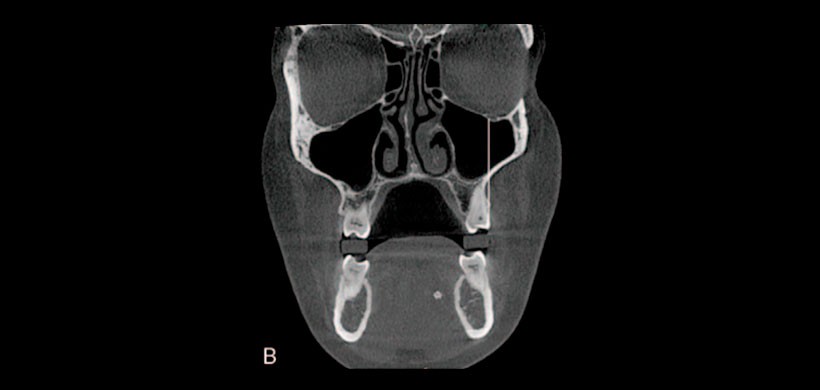

Figura 1: Visualización de foramen infraorbitario accesorios

Este estudio está destinado principalmente a evaluar la ubicación y el número de foramen accesorios infraorbitarios (AIOF), para medir la distancia entre foramen infraorbitario principal, AIOF (Figura 1) y secundariamente para determinar la posición del foramen infraorbitario en relación con las coronas del segundo premolar, primer molar y segundo molar del maxilar superior. (Figura 2)

Obteniendo como resultado que el foramen infraorbitario accesorio fue reconocido en el 29% de los casos pacientes entre los cuales 46.6% estaban presentes en el lado derecho, 31% en el lado izquierdo, y 22.4% localizado bilateralmente.

La posición frecuente del foramen infraorbitario se localizó en el eje de la corona del segundo premolar. La presencia de AIOF y la incapacidad de reconocerlo en la evaluación preoperatoria podría considerarse entre las otras razones de falla o anestesia incompleta.